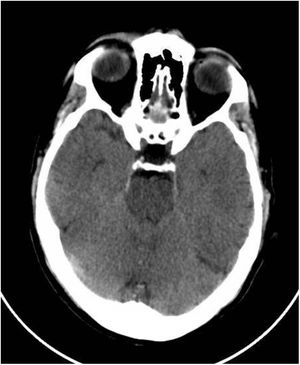

This was a 61-year-old male with no previous medical history, not vaccinated against SARS-CoV-2, who of his own free will began to consume chlorine dioxide daily in the belief that it would prevent the infection. After two weeks he developed gradual-onset encephalopathy symptoms with bradypsychia, derealisation, irritability and anxiety. Physical examination revealed dehydration of skin and mucosa. Brain computed tomography (CT) revealed cerebral oedema and idiopathic intracranial hypertension (Fig. 1). Fundus examination and lumbar puncture were normal. Blood tests showed: sodium 112 mEq/l; chlorine 77 mEq/l; plasma osmolarity 230 mOsm/kg; and uric acid 2.2 mg/dl; and fractional excretion of uric acid (FEUa) on admission was 15.4% and after 72 h with normalisation of natraemia, 11.4%. Venous blood gases: pH 7.42, bicarbonate (HCO3) 21 mmol/l, CO2 42 mmHg. No other findings of note. Urinalysis: sodium 72 mEq/l, potassium 30 mEq/l, chlorine 55 mEq/l, uric acid 15.4 mg/dl and osmolarity 224 mOsm/kg. The chlorine dioxide was immediately discontinued and treatment was started for water and electrolyte replacement progressively according to sodium deficit, with gradual restoration of neurological status and return to normal of analytical parameters (Table 1). A differential diagnosis of “other possible causes of hyponatraemia” was made.